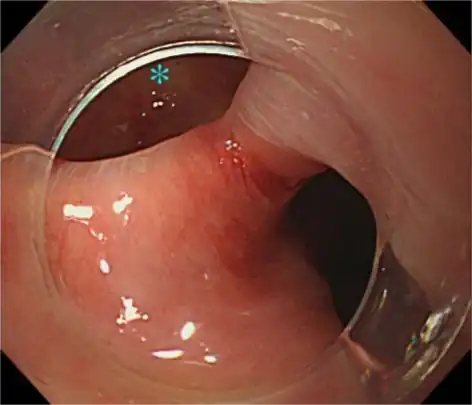

A combination of the simple barium swallow and a thorough endoscopy will normally confirm the diverticulum.[4]

If small and asymptomatic, no treatment is necessary. Larger, symptomatic cases of Zenker's diverticulum have been traditionally treated by neck surgery to resect the diverticulum and incise the cricopharyngeus muscle. However, in recent times non-surgical endoscopic techniques have gained more importance (as they allow for much faster recovery), and the currently preferred treatment is endoscopic stapling[5][6] (i.e. diverticulotomy with staples ). This may be performed through a diverticuloscope. Other methods include fibreoptic diverticular repair.[7]